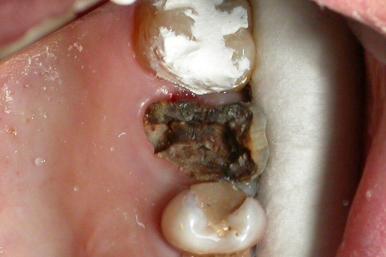

Przewlekłe zgorzelinowe zapalenie miazgi

Ta forma choroby dotyka tylko 2 pacjentów na 100 i charakteryzuje się zmianami wrzodziejącymi lub martwiczymi miazgi. Podczas opracowywania jamy zęba można wykryć ciemne resztki tkanki. W wielu przypadkach możliwe jest zachowanie zdrowej części miazgi. Przewlekłe zgorzelinowe zapalenie miazgi zdjęcie